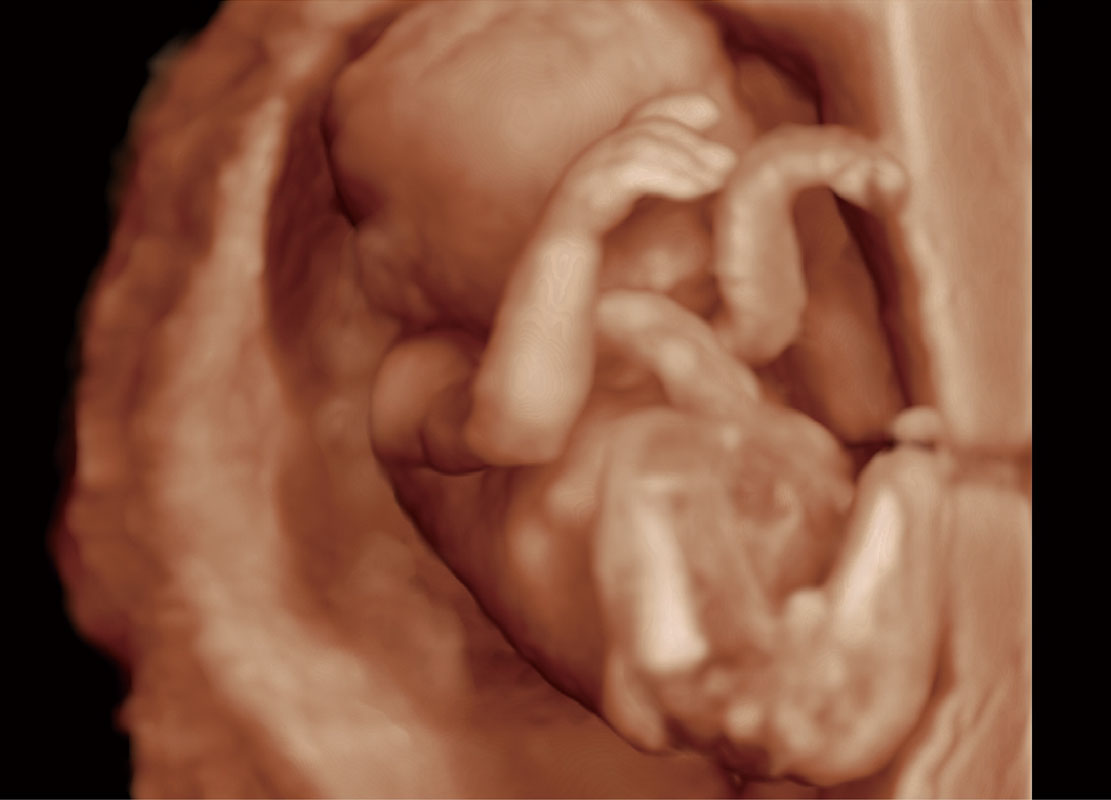

中晚孕筛查

P60提供简单易学易用的高端诊断工具,为您中晚孕筛查提供快速清晰的解剖信息。

& S-Fetus(meas.)

S-Fetus

S-Fetus能够助您在实时扫查过程中自动识别标准切面、自动测量并录入报告。一个按键,即可快速、高效地获取胎儿生理指标,简化您的产科检查操作。